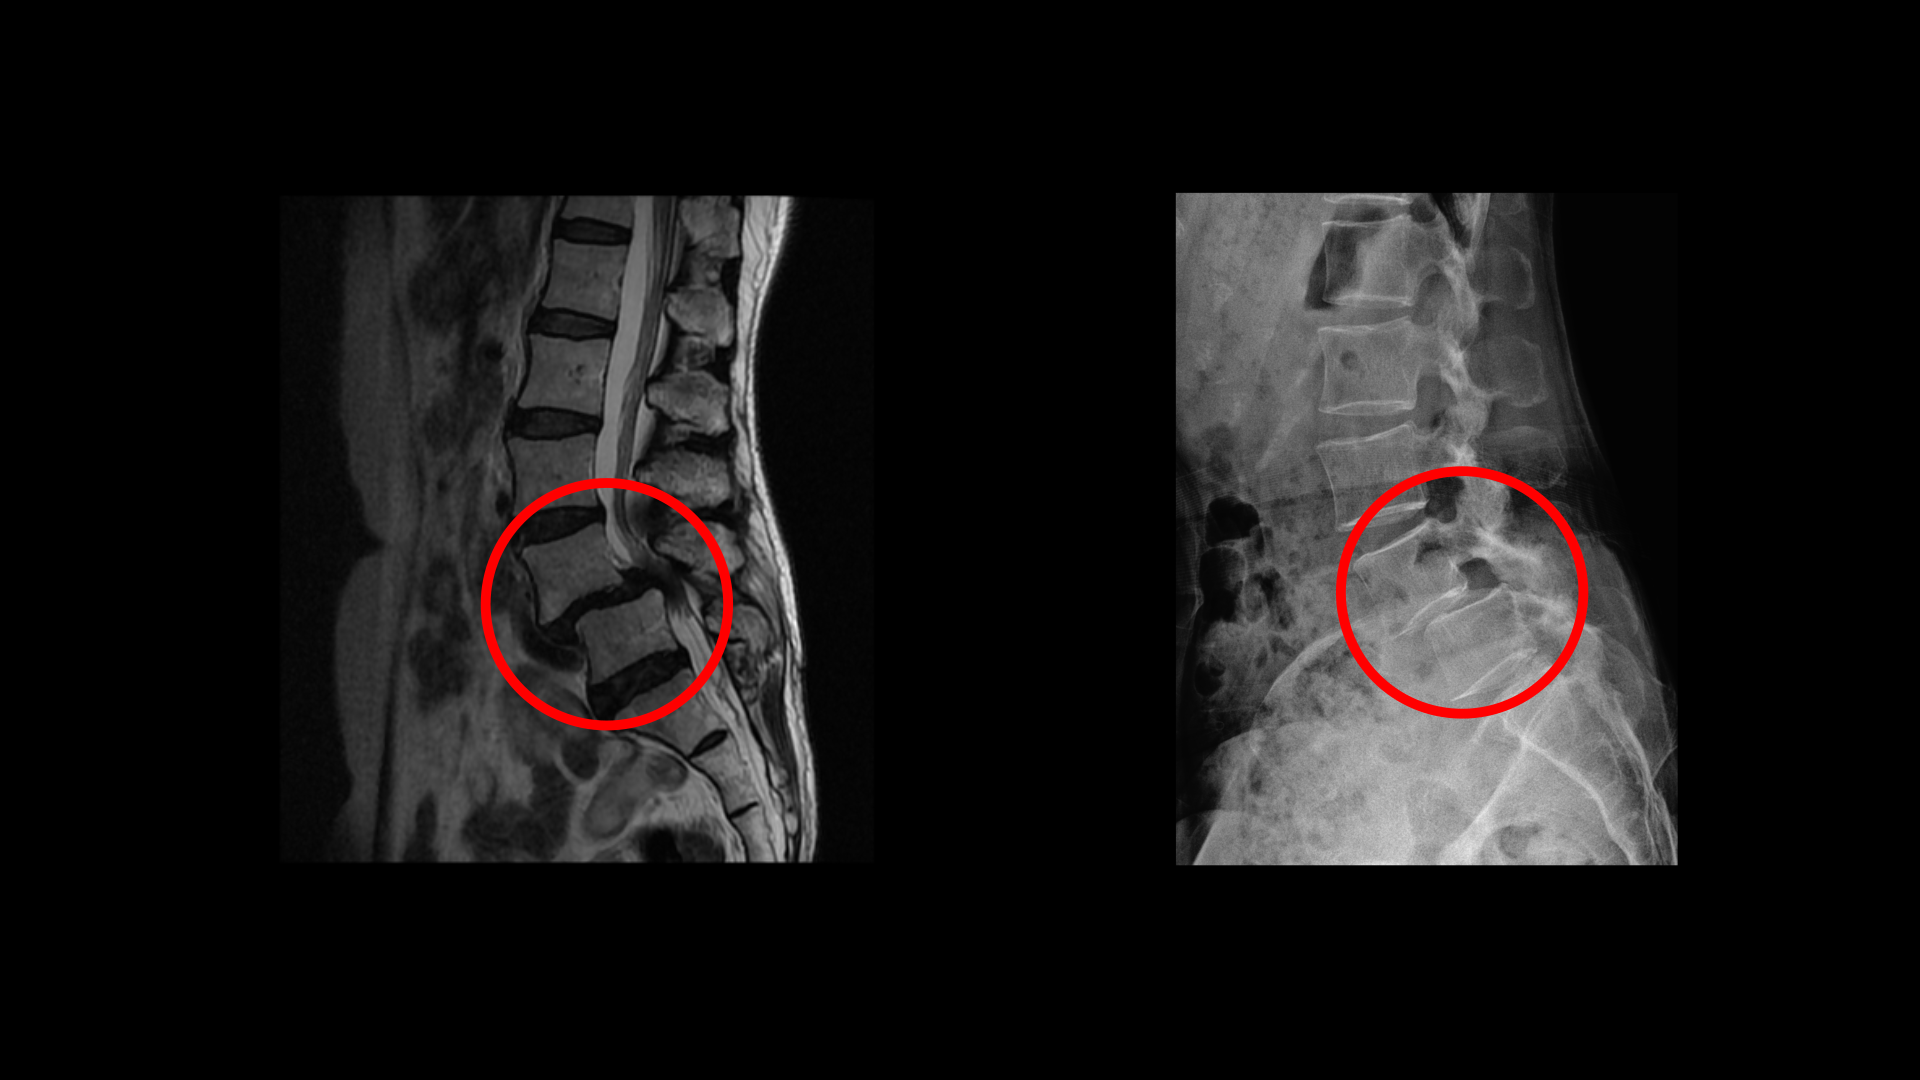

이 환자분 상태를 먼저 설명 드린 후 이분 말씀을 들어보겠습니다. 이분 MRI를 보면 전방전위증과 척추관협착증이 정말 심합니다.

위 뼈가 거의 절반 가까이 밀려 나가있고 두 마디의 척추관이 정말 심하게 막혀서 보시다시피 신경이 제대로 보이지 않습니다.

대학병원에 가서 MRI를 찍었는데 전방전위증, 척추관협착증이 있다고 했어요. 전방전위증이 2단계로 심하니까 나사를 박자고 했어요. 나사 박고 생활하면 훨씬 나을 거라고 했어요. 근데 저는 수술하는 걸 원치 않아서 집에 가서 생각해 보겠다고 하고 그냥 나왔어요.